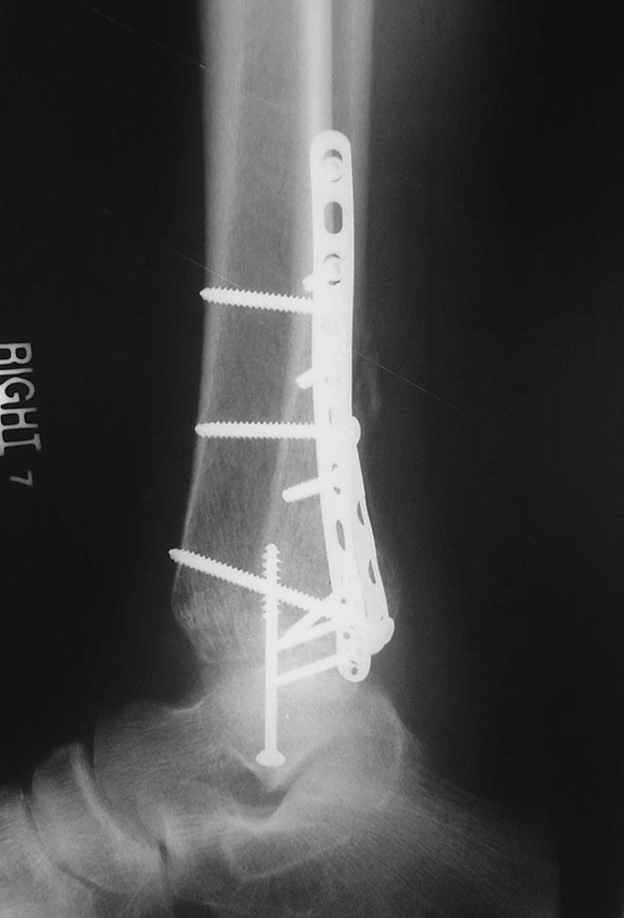

Я вот все в толк не возьму смысл отдельной фиксации малоберцовой кости пластинкой, если все равно будет аппарат с фиксацией стопы, т.е. возможностью провести спицы в пятку, таран, наружную лодыжку и еще черт-те куда. Остеосинтез пластинкой выглядит логичным в случае, когда наружная фиксация планируется как временная. Но тут-то аппарат будет окончательным фиксатором.

Еще, кстати, о фиксации лодыжки, если уж непременно хочется ее отдельно стабилизировать - при таком характере перелома замечательно должен сработать предложенный проф. Лазаревым с соратниками способ фиксации напряженной V-образной спицей. Опять же, открытая репозиция не нужна, мы делаем непрямую репозицию именно аппаратом. В приложении пример, там перелом малоберцовой куда менее поперечный, чем в данном случае, но все равно получилось закрыто без пластинки.

I can't realize why plate fibula separately if anyway external fixator including the foot is planned, i.e. one may insert wires to the talus, calcaneus, lateral malleolus and anywhere else. Plating looks reasonable if only temporary ex-fix is planned, but in the case it will be definitive.

A propos fibular fixation if one is eager to stabilize it separately. In the fracture pattern a way of closed fixation by V-shaped stressed wire (advanced by colleagues from Moscow, prof. Lazarev A.F. et al.) must be excellent. We use indirect closed reduction by the external fixator. Example attached, that fibular fracture is even more suitable for plating but the wire did the job.